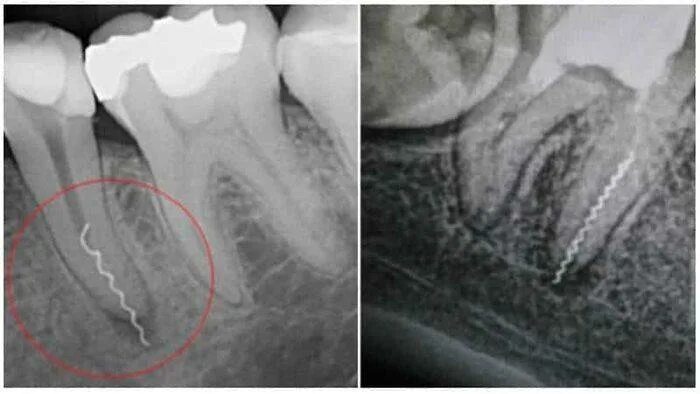

Удалить нервы запломбировать